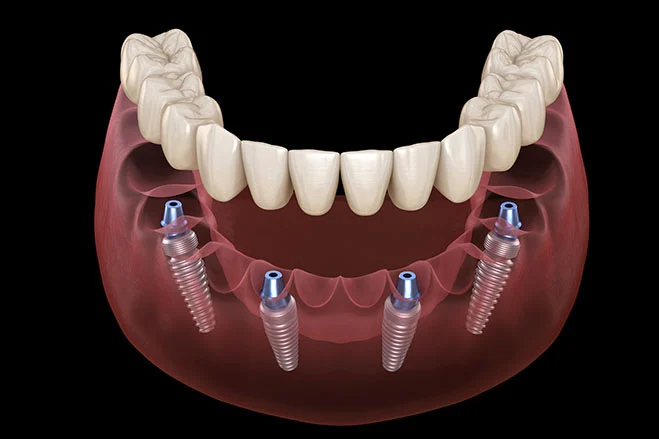

- Full Arch Restoration – Replaces a complete set of teeth using just four dental implants.

- Minimally Invasive Procedure – Performed in a single sitting under local anesthesia.

- Fixed Non-Removable Teeth – Offers a stable and permanent solution without removable dentures.

- Faster Recovery & Fewer Surgeries – No need for multiple surgeries or complex bone grafting.

No, All-on-4 dental implants are not removable. They are a permanent set of teeth secured on four titanium implants, offering a stable and long-lasting solution.